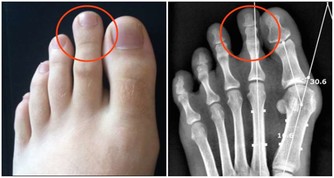

慢性型早期會出現煩躁、食慾減退、低熱、多汗、脫髮、以後有典型的骨痛症狀。